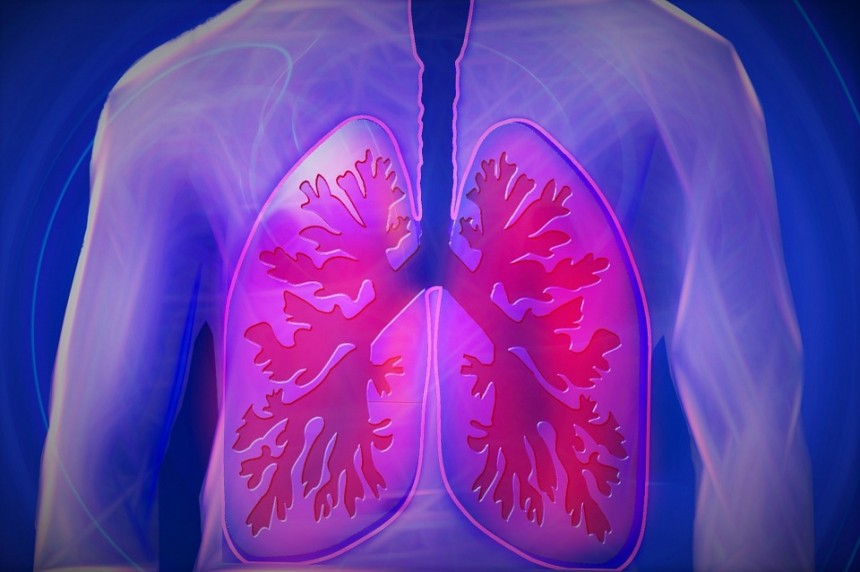

Dokazana je neverovatna sposobnost cimeta protiv infekcija izazvanih kvascima, kao što je kandida. Naročito gljivične infekcije stopala, bivaju sa velikim uspehom tretirane primenom eteričnog ulja od štapića cimeta. Antibakterijsko delovanje cimeta se ispoljava najčešće protiv stomačnih infekcija, izazvanih salmonelom, listerijom, helicobakterijom i ešerihijom. Ulje od cimeta ima i antivirusno dejstvo, posebno kada su u pitanju adenovirusi koji izazivaju infekcije disajnih puteva.

Ulje od cimeta ima i antivirusno dejstvo, posebno kada su u pitanju adenovirusi koji izazivaju infekcije disajnih puteva.

Olakšava simptome gripa, prehlade, bolova u grlu i promuklosti